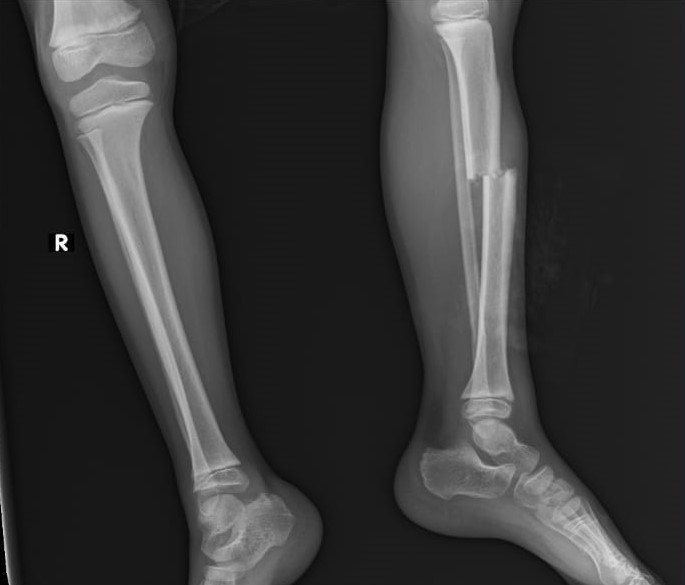

Antalya'da su içmek için okul bahçesine yapılan hayrata gidip üzerine çıkan 7 yaşındaki Eymen, mermer bloğun çökmesi sonucu 1,5 metre yükseklikten beton zemine düştü. Mermerlerin altında kalan küçük çocuğun kaval kemiği kırıldı, vücudunun çeşitli bölgelerinde dikiş atılması gerektiren kesiler oluştu. Anne, "Çocuğumun ayağı kırık, iç kanamadan şüpheleniyorlar. Kulağının arkasında 15 dikiş var. Ölümle burun buruna gelmiş" diyerek, gözyaşı döktü.

Olay, dün saat 16.00 sıralarında Kepez ilçesi Mehmet Akif Ersoy Mahallesindeki Şerife Tufan İlkokulu'nda yaşandı. Edinilen bilgiye göre, okulun karşısında akrabalarının işyerinde bulunan Atiye - Hasan Çiçek çiftinin 7 yaşındaki çocukları Eymen, annesine eğitim gördüğü okulun bahçesindeki hayrattan su içmek istediğini söyledi. Arkadaşlarıyla birlikte okul bahçesine giren Eymen, çeşmeden su içtikten sonra hayratın üzerine çıktı. Bu sırada üst kısımdaki mermer blok bir anda çöktü. Diğer çocuklar kaçarak olayı yara almadan atlatırken, minik Eymen yaklaşık 1,5 metre yükseklikten düşüp, mermer ve beton parçaların altında kaldı. Diğer çocukların durumu bildirmesi üzerine olay yerine gelen anne Atiye Çiçek, çocuğunu kanlar içerisinde görünce büyük bir şok yaşadı. Sol bacak kaval kemiği kırılan, kafa ve vücudunun çeşitli noktalarında kesiler oluşan küçük Eymen, Kepez Devlet Hastanesinde tedavi altına alındı.